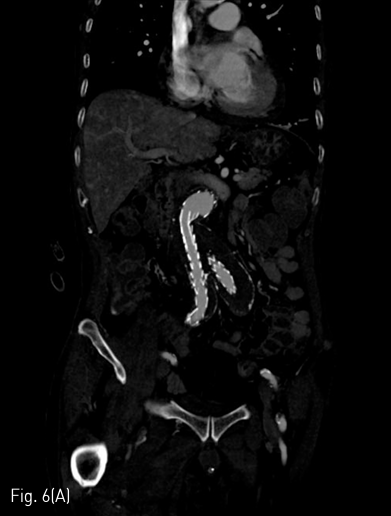

시술 1개월 뒤 시행한 조영증상 CT에서 양측 장골 분지 인조혈관 내강은 잘 유지되었다(Fig. 6A&B).

Fig 6A

(A,B) CT angiography obtained 1 month later the procedure shows patent intraluminal space of bilateral iliac limb graft.